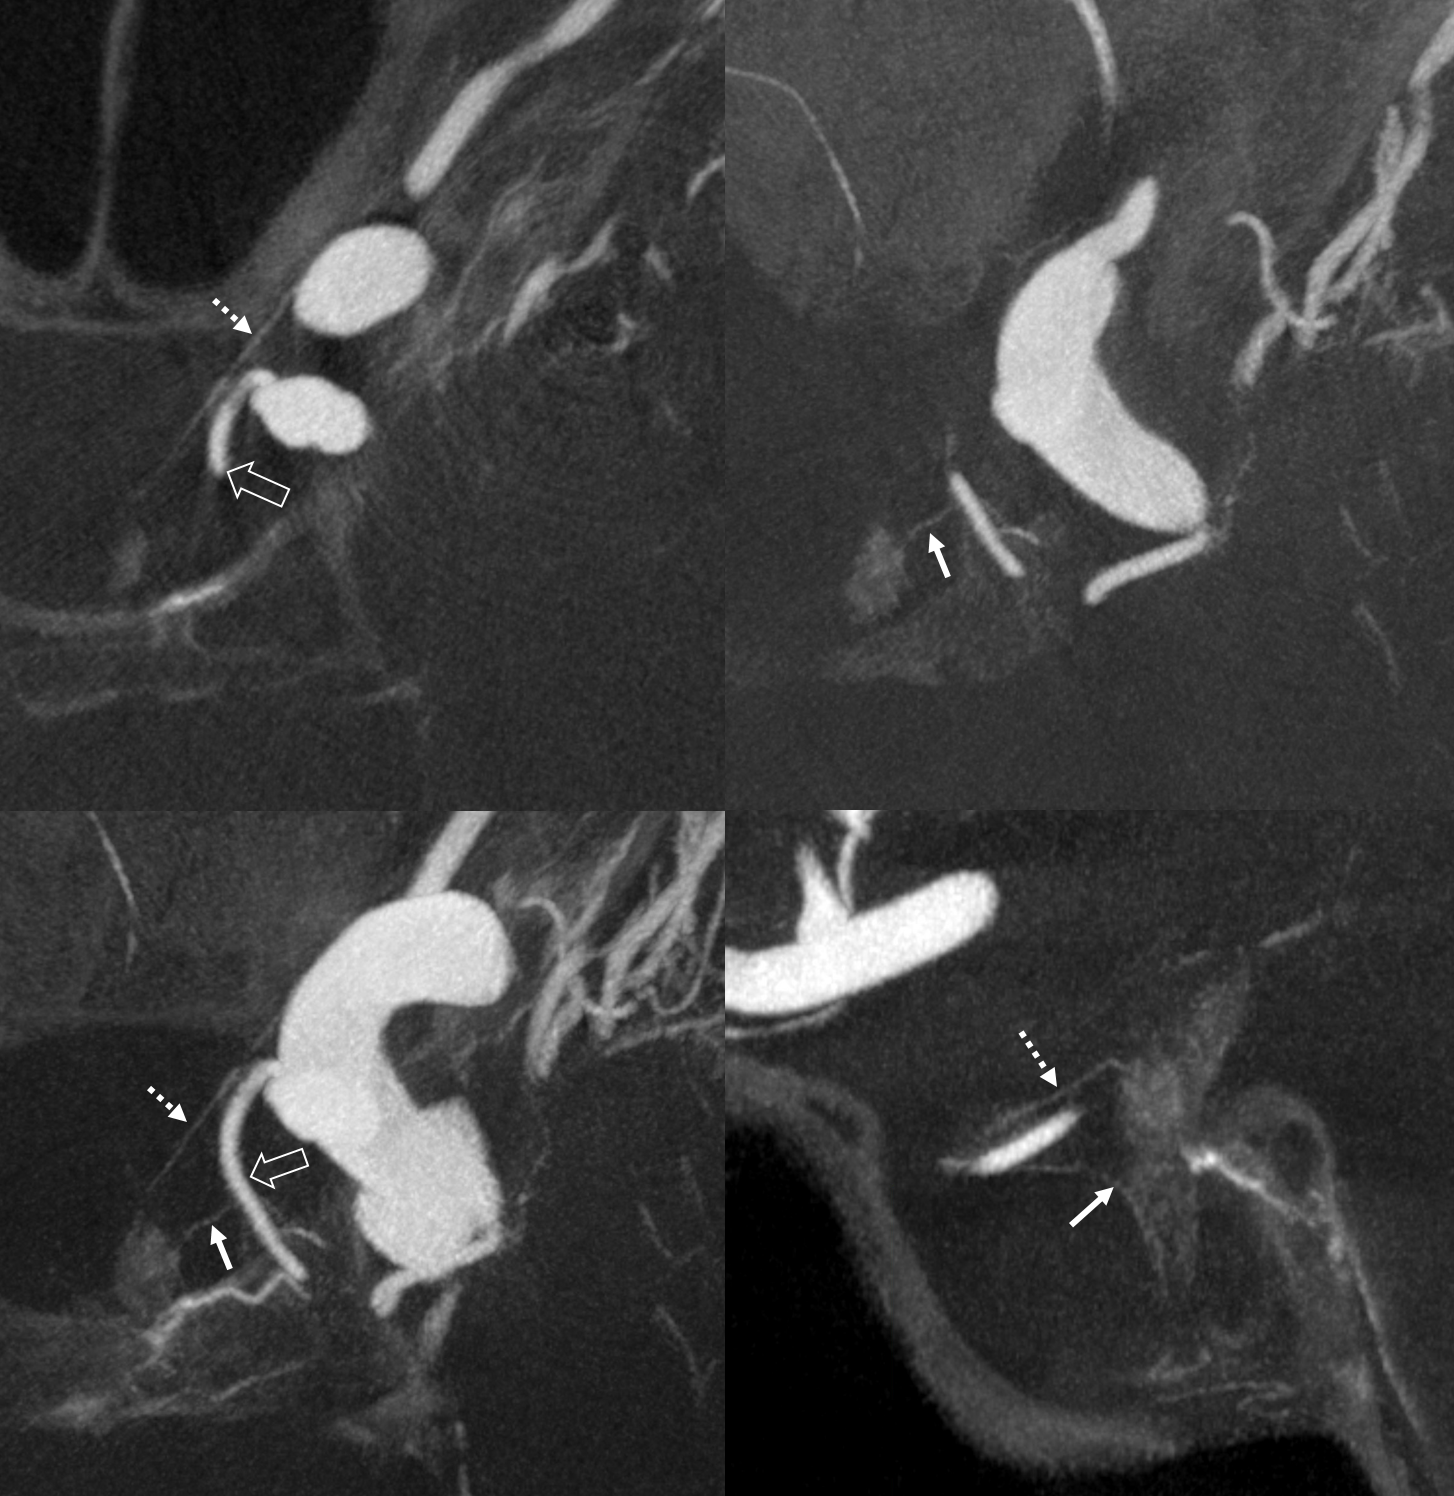

What supplies the bulk of optic nerve? Central Retinal artery is for the distal portion of nerve and retina. What about the rest — intracranial, intracanalicular, proximal intraconal segments? The answer is not clear (let me know if you do), but i believe the bulk of it comes from the superior hypophyseals. It is probably in balance with the recurrent branch of the central retinal artery. Below is an example of an especially prominent proximal-most superior hypophyseal (arrows) supplying the pituitary stalks and optic nerve in the canalicular and intracranial locations. Note how well one can see the branch in coronal view (bottom left image). In this case there are two large superior hypophyseals — the more distal one (dashed arrows) supplies predominantly the pituitary stalk. The inferior hypophyseal artery is marked by arrowhead. Lower right image is coronal.

Movie is the best way

Here too superior hypophyseal (arrow) supply of the intracranial optic nerve (oval) and possibly chiasm is shown definitively (lower right image is coronal)

No annotations

Best seen in this movie (pause to scroll)